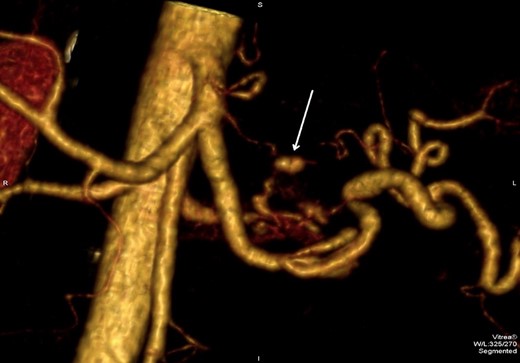

3D reconstruction images of the CTA revealed that the pseudoaneurysm was localized on an unnamed vessel branching directly from celiac trunk (Fig. 5). This deemed not suitable for endovascular embolization due to its size.

3D CTA reconstruction demonstrates the pseudoaneurysm (arrow) originating from the unnamed vessel.